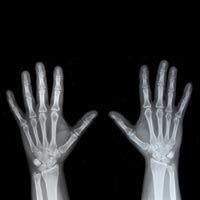

Группа специалистов на протяжении 2007–2012 гг. регистрировали данные о пациентах с переломами дистального отдела лучевой кости (перелом запястья). С их слов, такой перелом свидетельствует о потере костной массы и за 10–15 лет предшествует перелому бедра. Знание этой специфики помогает понять важность ранней оценки плотности костной ткани и при необходимости — провести лечение, направленное на профилактику переломов в будущем.

Существующие рекомендации обязательного скрининга плотности костной ткани у пациентов с переломом шейки бедра непопулярны среди практикующих врачей, особенно это относится к скринингу у мужчин. Т. Розенталь надеется, что такая нездоровая тенденция не укоренится при лечении переломов запястья.

Результаты исследования позволяют предположить необходимость введения обязательного скрининга плотности костной ткани у мужчин в возрасте старше 50 лет с переломом дистального отдела лучевой кости и дальнейшего назначения медикаментозной коррекции.